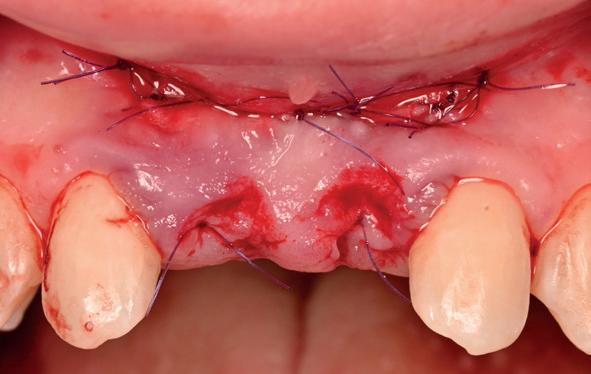

• Aanvulling zachte weefsels met de VISTA techniek en een vrij gingivatransplantaat uit het palatum links en direct dragen van de essix retainer

Voor de aanvulling zachte weefsels chirurgie werd gekozen voor de VISTA techniek, hierbij worden er twee incisies partial thickness flap hoog in de mucosa gemaakt, waarna er ruimte vanuit de incisies wordt getunneld tussen de gingiva en het periost door middel van VISTA tunnel instrumenten. Uit het palatum links werd een vrij gingivatransplantaat geoogst van 15x10 mm met een dikte van 3 mm, die voor inhechten werd geëpithelialiseerd. Als het epitheel niet wordt verwijderd, kan deze graft door

de mucosa heen groeien, dat ten koste gaat van de esthetiek. In het donorgebied wordt een collageen spons ingehecht, waardoor de patiënt daar minder last van heeft. Het bindweefsel wordt door de hul-

pincisies met hechtingen naar het buccale en coronale deel getrokken en aldaar ingehecht. Met twee incisies werd ook de emergence profile gecreëerd (afbeelding 6-13). Voor een goede genezing van het

5. Beginsituatie voor behandeling

6. VISTA techniek twee hulp incisies

7. Vervaardiging tunnel met tunnelinstrumenten

8. Geoogst bindweefseltransplantaat uit palatum

9. Na de-epithelialiseren van transplantaat

10. Inhechten van een collageenspons in het donorgebied

11. Middels hechtingen het op de juiste plek trekken van het transplantaat

12. Transplantaat ingehecht

13. Occlusaal beeld verdikking van de zachte weefsels